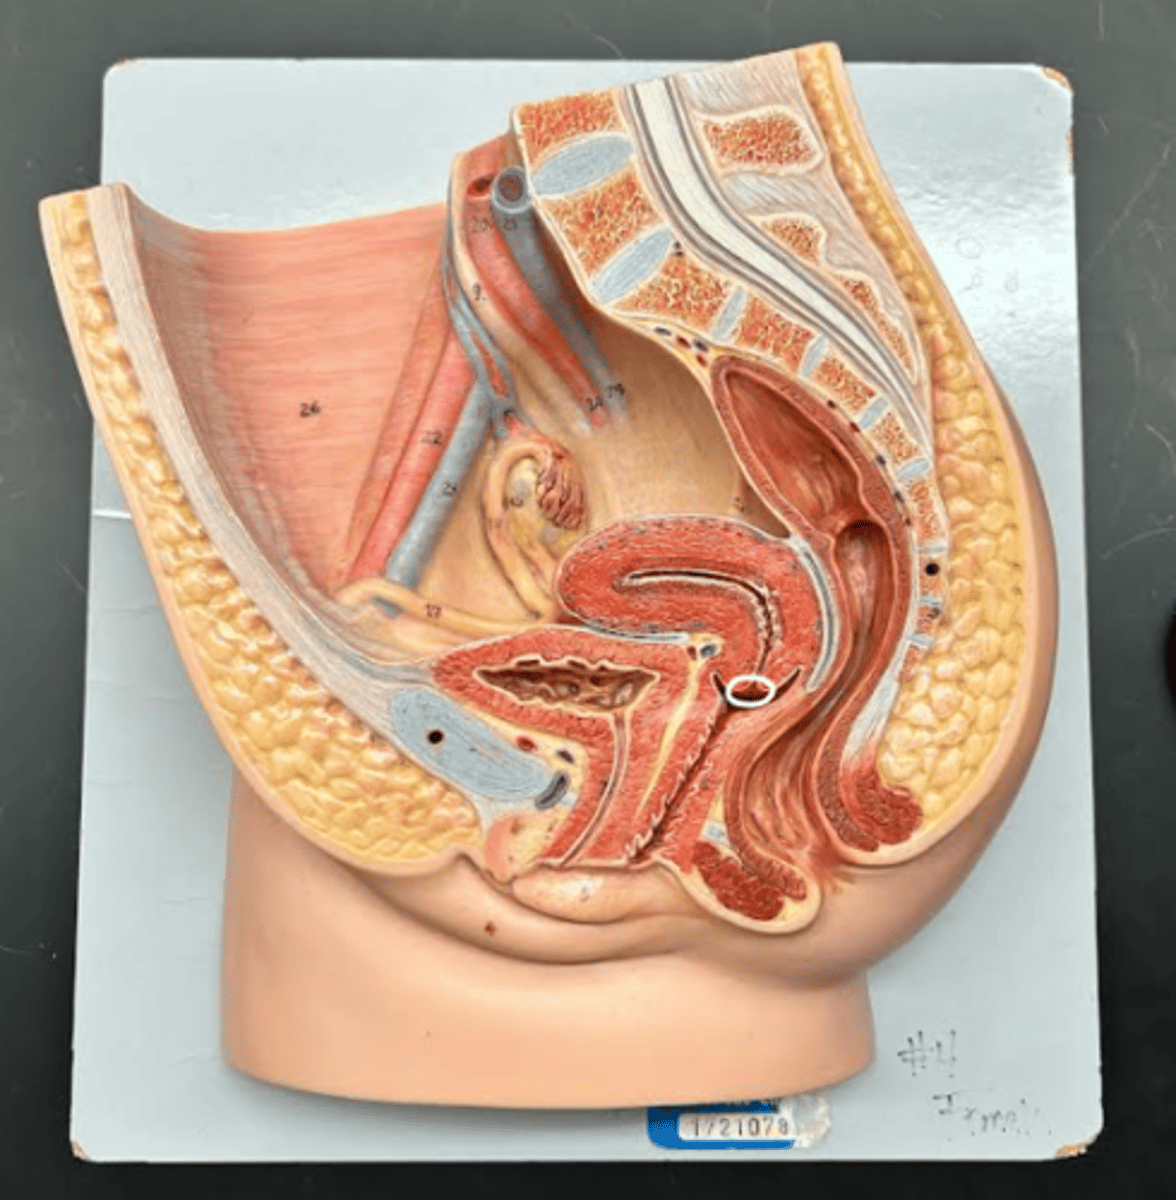

Chapter 29 Anat Phys: Female Reproductive System

Vagina

Vaginal orifice

Hymen

Vaginal fornix

Ovary

Fallopian tube

Fimbriae

Infundibulum

Ampulla

Isthmus

Uterus

Perimetrium

Myometrium

Endometrium

Fundus

Body of uterus

Cervix

Internal os

Cervical canal

External os

Labia majora

Labia minora

Prepuce

Vestibule

Clitoris

External urethral orifice